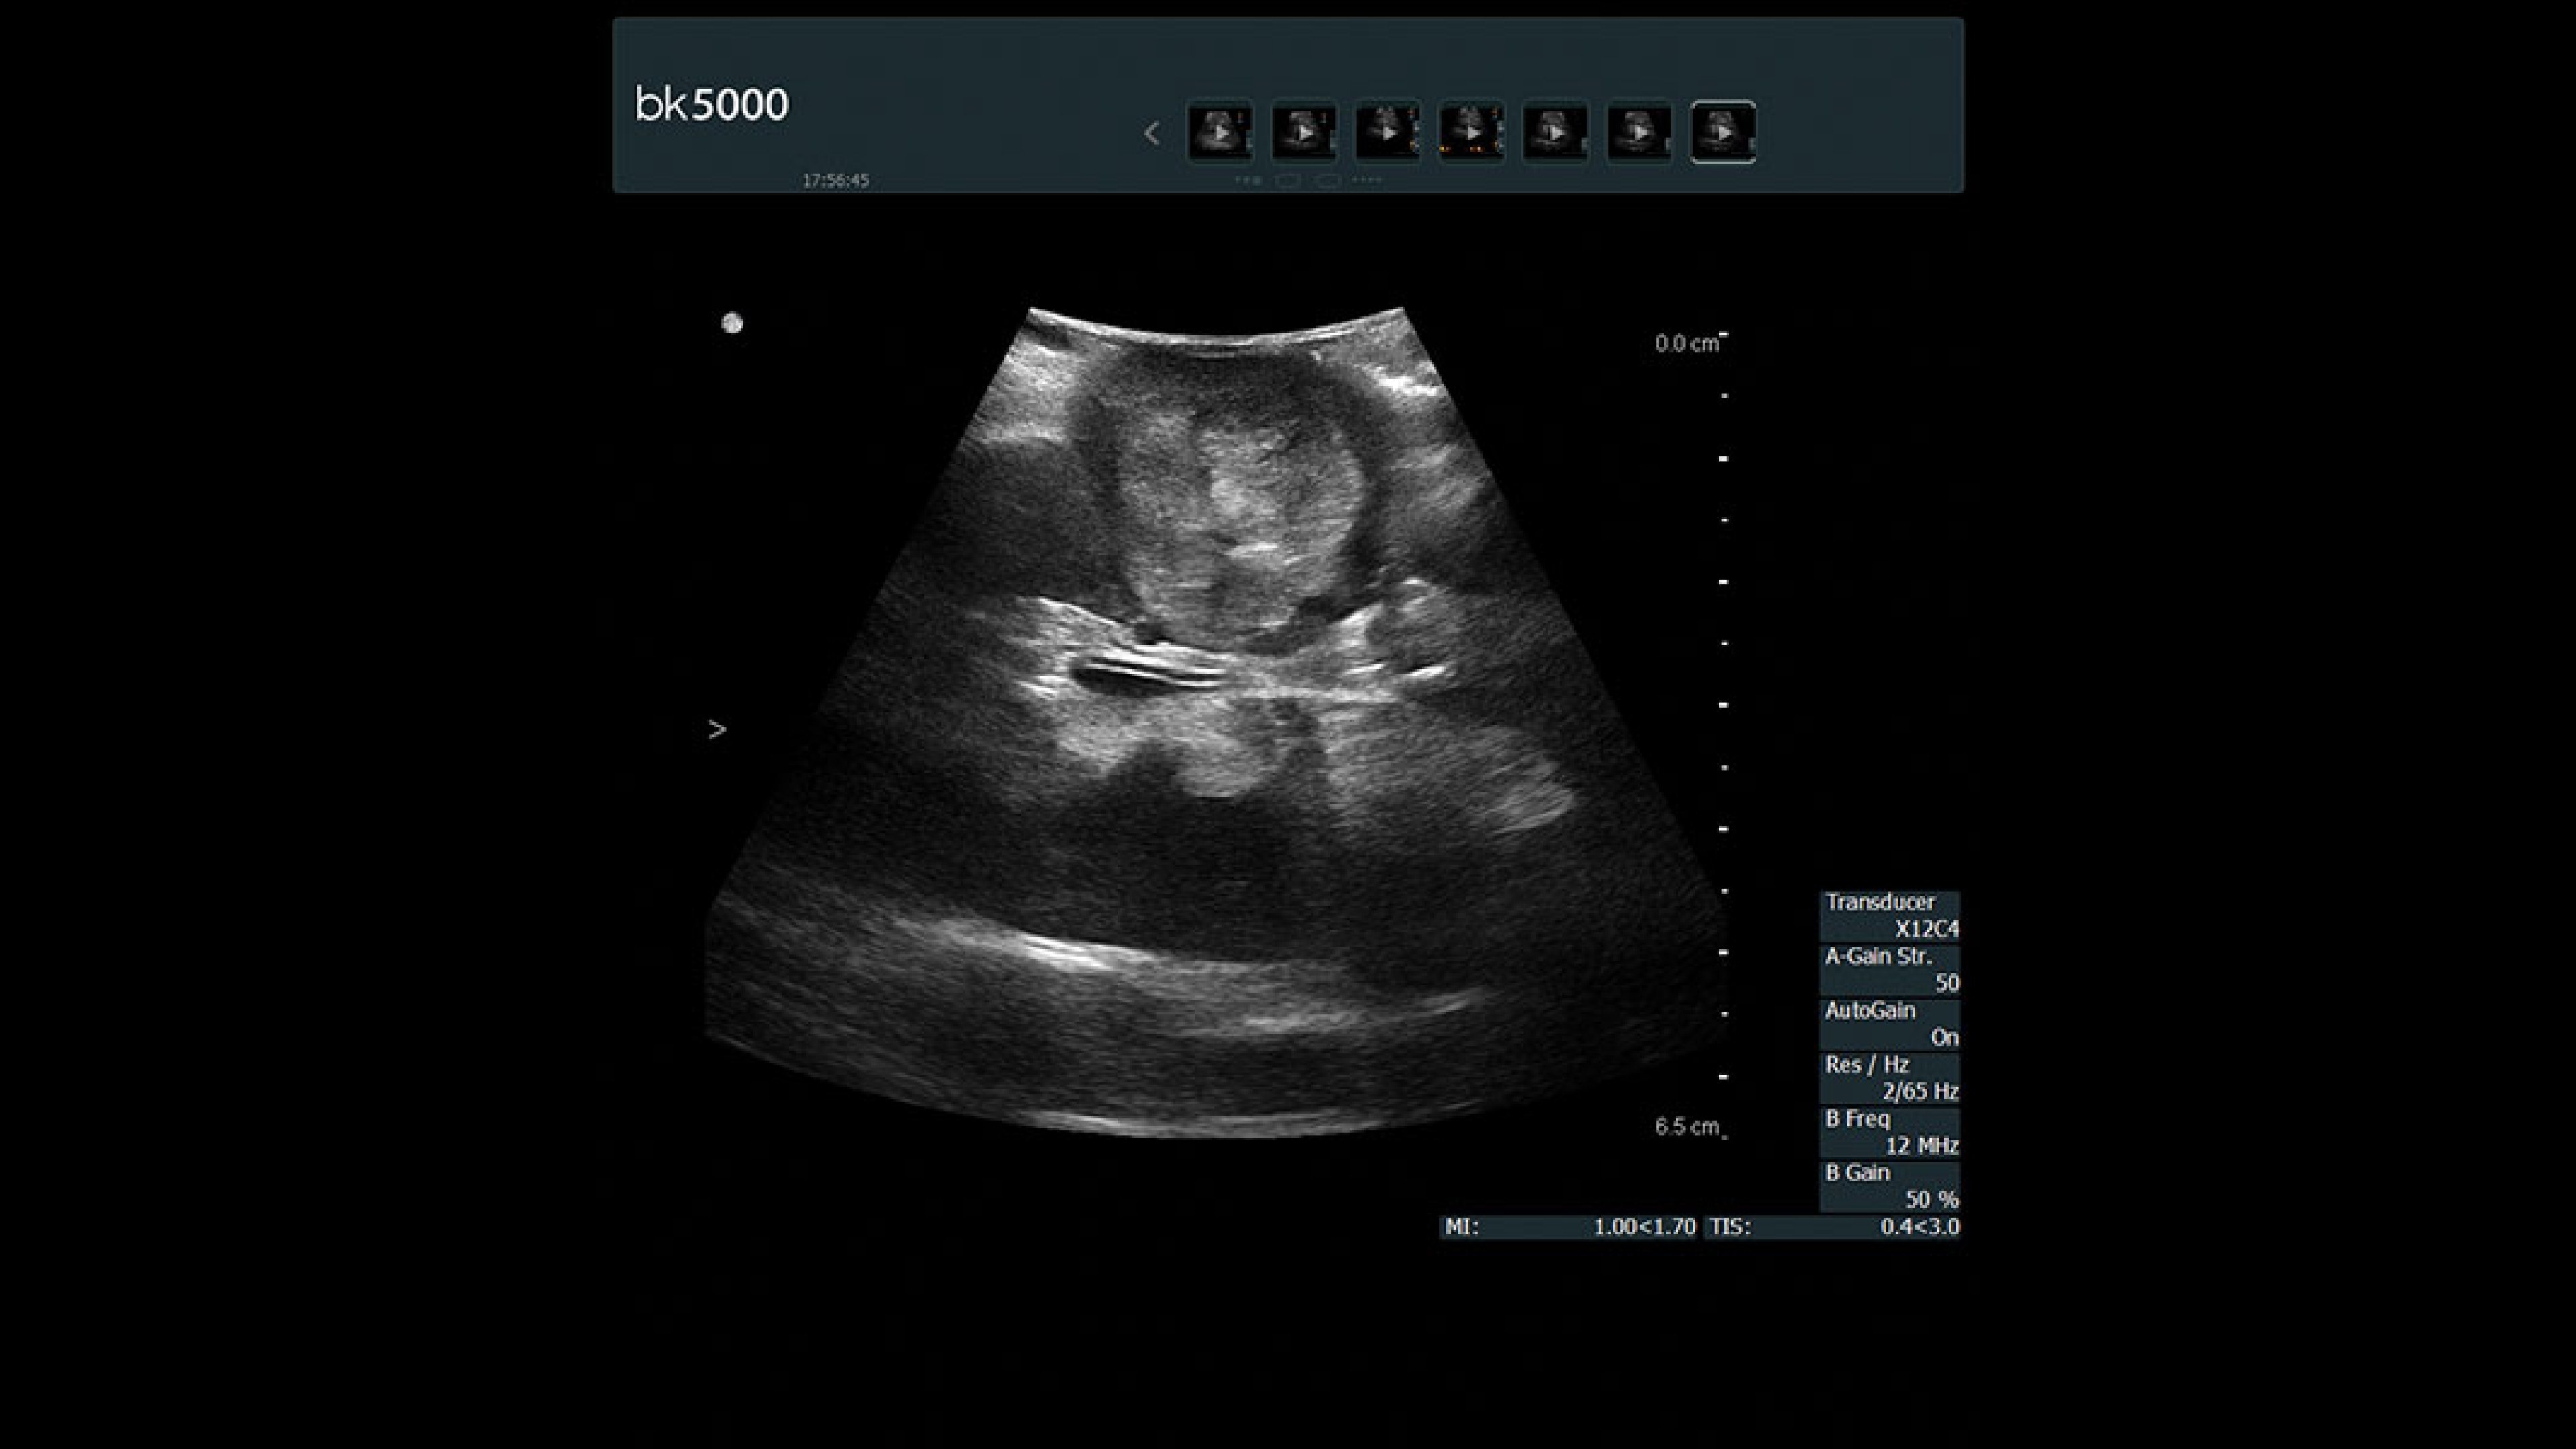

bk5000 ultrasound system

Experience the bk5000 built with remarkable image clarity and advanced features for intraoperative, robotic, and neurosurgery, enhancing surgical precision.

Precision imaging for refined surgical outcomes

The bk5000 ultrasound system offers unmatched image clarity and advanced features tailored for intraoperative, robotic, and neurosurgery applications. With intuitive controls and specialized tools, it enhances surgical precision, streamlines workflows, and ensures reliable performance in demanding environments. Experience the difference in patient care and surgical efficiency with the bk5000.

Intraoperative surgery

Designed for surgery

The bk5000 surgical system advances intraoperative surgical procedures by helping you navigate and identify lesions and anatomical structures in real-time. This is particularly important as the data obtained from a preoperative CT or MRI scan can be outdated at the time of surgery.

• Highest quality images: Clearly see the margins of a lesion and determine the best course of action.

• Advanced graphics processing technology: Provides immediate, auto-optimized images for faster information retrieval.

• Sterilizable remote control: Convenient control of the system in the sterile field.